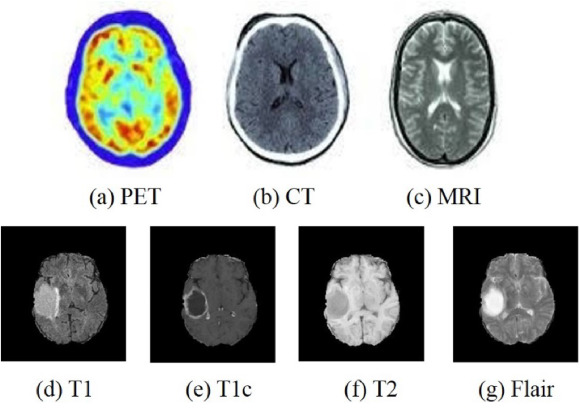

The combination of PET and MRI, PET and CT has been recognized as a valuable method for screening and diagnosing various diseases [31, 127, 87, 239, 12]. The PET scan is preceded by the administration of a radioactive agent to the patient. This allows doctors to determine the metabolic processes in which the brain tissue is involved [17]. Compared to other imaging methods such as CT and MRI, PET has a high sensitivity and can detect lesions even if MRI/CT does not yet show abnormalities. PET also has high specificity, making it possible to determine whether a tumor is malignant based on its metabolism at the time of MRI/CT detection [150]. However, because PET scan lacks information about organ anatomy, they should be conducted in conjunction with CT/MRI scans [7]. Indeed, the combination of PET and MRI/CT scans provides structural and functional information related to various diseases, improving the effectiveness of diagnosis. Fig. 5 shows the images of PET, CT, and MRI, as well as several sequences of MRI.

Refer to caption

Fig. 5: (a)-(c) are the images of PET, CT, and MRI. (d)-(g) are the different sequences of MRI. Images from Zhou et al. [259].

Neurology and neurosurgery frequently use MRI. Different MRI images can be obtained by changing the factors affecting the magnetic resonance (MR) signal, and these different images are referred to as sequences. Depending on the sequence used, the behavior of tumors may vary, and it is essential to use multiple sequences to accurately determine tumor location and size [158]. T1-weighted (T1) and T2-weighted (T2) MRIs are the most common MRI sequences. Tomographic anatomical maps can be observed with the T1 sequence, and the T2 sequence clearly shows the location and size of the lesion [123]. The Fluid Attenuated Inversion Recovery (Flair) sequence provides better visualization of the area around the tumor site, making it easier to detect the tumor’s boundaries [78]. Furthermore, contrast-enhanced T1-weighted (T1c) sequences can be used to detect intra-tumor conditions and distinguish tumors from non-tumorigenic lesions [104]. T2 and Flair are suitable for detecting tumors with peritumoral edema, while T1 and T1c are suitable for detecting tumors without peritumoral edema [259].